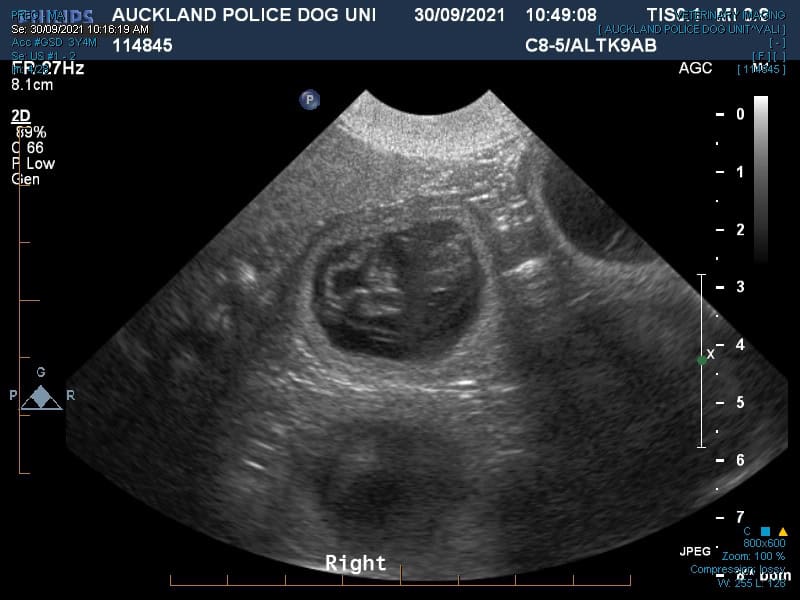

Vali is a 3-year-old German Shepherd who works for the Auckland Police Dog Unit. She came in to see our Mount Albert team at the end of September for a pregnancy ultrasound to check for a positive pregnancy. On this visit, Dr Mike Coleman confirmed multiple viable gestational sacs, but we were unable to say how many there were.

an ultrasound showing Vali's multiple gestational sacs

It’s tricky to do this when there are multiple sacs at the best of times, let alone when you are doing an ultrasound on a very active police dog. Vali is a very strong dog, as all police dogs are and so getting her to stay still while we tried to count the number of pups was a challenging task. Vali is a dog who knows her own mind and that meant that while on this visit we were able to confirm a pregnancy, we had to defer counting how many puppies there might be to another visit.